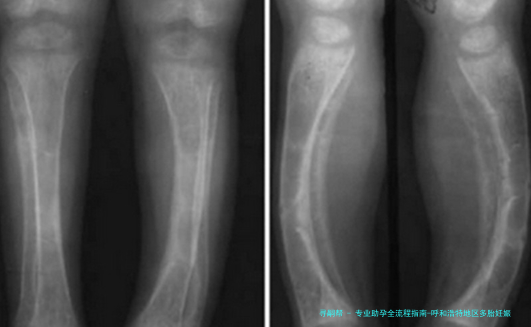

对胎儿来说,多个胎儿妊娠明显增加流产风险(提高5-10倍),导致低出生体重、发育迟缓等问题的发生率明显增高。早产儿各器官发育未成熟,易出现呼吸窘迫综合征、新生儿颅内部出血等多种并发症, *** 妊娠早产儿的死亡率约为单胞胎未足月产儿的2-12倍。